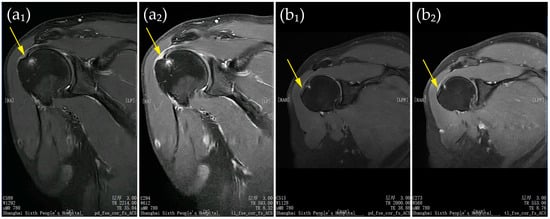

Figure 1 presents representative shoulder MRI scans of two patients at baseline.

(a,b) Representative shoulder MRI scans of two patients at baseline. Panels (a1,b1) show proton density–weighted fast spin-echo images in the coronal plane with fat saturation and autocalibration for parallel imaging; panels (a2,b2) show T1-weighted fast spin-echo images in the same plane with identical parameters. Yellow arrows indicate partial-thickness ST tears. All patient-identifying information has been removed to protect privacy.